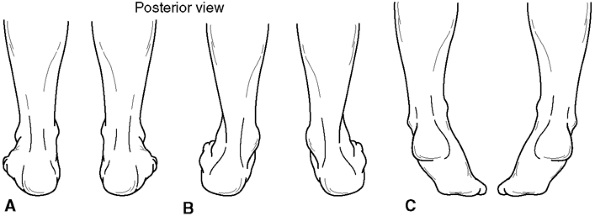

Hindfoot varus and valgus: This position

is measured in stance as the angle between the long axis of the tibia

and the long axis of the hindfoot, either in varus, valgus, or neutral (Fig. 30.4 A and B). -

Normal hindfoot mobility. This is measured by looking for the hindfoot to tip into mild varus as the patient rises on the toes (Fig. 30.4C).